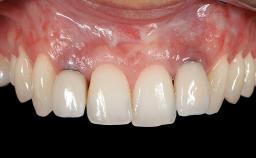

Implant Placement in the Esthetic Zone and Coverage of Multiple Gingival Recessions

This case illustrates use of a modified ‘tunnel’ technique, which has been shown to be highly effective in root coverage procedures. The tunnel technique is used to achieve soft-tissue augmentation across the anterior area, including the planned implant site, using collagen matrix as grafting material. The patient is a 47-year-old woman with high esthetic expectations. Her main concern was the appearance of the anterior teeth and their “elongation”.

Patient's Esthetic Expectations Low Medium High

Esthetic Risk High